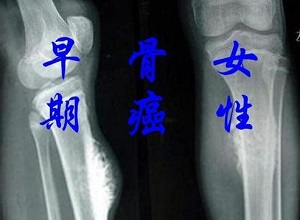

郑州肿瘤中医师王卫昌:骨癌是怎么引起的?这5个危险因素要谨防.不同的癌症有不同的危险因素,大多数骨癌患者没有明显的危险因素,但以下因素会增加患骨癌的风险。

骨癌是怎么引起的?我们必须警惕这五个危险因素

虽然骨癌不像其他癌症那样常见,但骨癌的发病率每年都在增加。了解骨癌的这些危险因素并定期检查有助于骨癌的早期治疗。